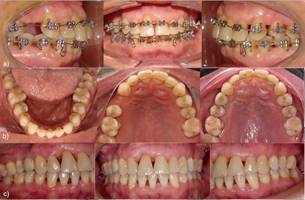

Tratamiento de ortodoncia: Al finalizar la segunda TSP se inició el TO por especialistas. Se planificó un tratamiento ortodóncico no conservador, con exodoncia del diente 3.1 para solucionar el apiñamiento y proinclinación incisiva inferior, permitiendo corregir el overjet y overbite y adicionalmente, mantener las relaciones oclusales en los sectores laterales. Para ello se utilizaron aparatos fijos prescripción Roth 0,022” (brackets Balance, GAC®, EE. UU.) en ambas arcadas, con tubos de cementado directo en molares (Ovation, GAC®, EE. UU.). En los incisivos superiores se realizó una cementación estratégica de brackets, posicionándolos más hacia cervical, siguiendo el nivel óseo remanente, observado en la radiografía panorámica. En dientes con pérdida ósea, el centro de resistencia se desplaza apicalmente, lo que determina que al aplicar una fuerza el momento generado sea mayor. La cementación estratégica permite acercar los brackets al centro de resistencia de cada diente y con esto, disminuir el momento que se genera al aplicar una fuerza ortodóncica. En el resto de los dientes, los brackets se cementaron en forma convencional, en el centro de la corona clínica. La paciente fue citada a control cada 4 semanas. En la arcada superior, el primer arco utilizado fue un alambre twist flex 0,0175” con dobleces compensatorios en los incisivos según la posición de los brackets. Una vez corregidas las rotaciones, a los 3 meses de TO, se inicia la intrusión con arco de acero 0,014” llegando como máximo a un acero 0,016”. En cada control se modificaron gradualmente los dobleces compensatorios (menos de 1 mm.), para lograr la intrusión de las piezas extruídas (Figura 5). El uso de arcos de acero permite entregar fuerzas interrumpidas, que son aquellas que disminuyen a cero entre activaciones, lo que posibilita un período para la reorganización de los tejidos antes de volver a aplicar la fuerza. La alineación y nivelación inferior se obtuvo utilizando arcos de NiTi 0,012” y luego a los tres meses se pasó a un acero 0,014” por dos meses más. Para la retrusión y cierre de espacio de la exodoncia del incisivo, se usó un arco de acero 0,016” con ansas cerradas distales a 3.2 y 4.2 (Figura 6a), reactivadas control por medio. La fase de finalización, en ambas arcadas, fue obtenida con arcos de acero 0,016” compensados y cinchados. Cabe recalcar, desde un punto de vista ortodóncico, que el objetivo principal en este tipo de pacientes es corregir la migración dentaria patológica, para lo cual se debe mantener un muy buen control de biofilm dental, eliminar las fuerzas oclusales traumáticas, con niveles de fuerza muy bajos y autolimitados, sobretodo en la etapa de intrusión. Luego de 26 meses de tratamiento, se lograron los objetivos del TO y se realizó retiro de aparatos. Se dejó con contención fija en ambas arcadas (alambre twist flex 0,175”), en incisivos superiores y de canino a canino inferior (Figura 6b), y además con una placa Hawley de asa larga, como contención removible en la arcada superior, de uso día y noche por los primeros seis meses y luego sólo noche hasta completar los dos años de uso. Luego de ello, se fue disminuyendo progresivamente hasta que en el lapso de los dos años subsiguientes se eliminó la contención removible, manteniéndose las contenciones fijas en forma permanente.

Durante todo el TO se mantuvo la TSP en intervalos de 3 meses, controlando cuidadosamente el biofilm dental. Posteriormente, la paciente fue sometida a una cirugía de implante dental para reemplazar el diente 1.4 ausente. Se realizó la evaluación clínica y radiográfica con Cone Beam del sextante 1 con el cual se planificó la posición, inclinación y distancias necesarias con los dientes adyacentes. El implante fue de 4,2 mm. ø x 13 mm. sin necesidad de injerto óseo, no se observaron dehiscencias ni fenestraciones del hueso alveolar en el momento de la cirugía, con el cual se obtuvo la estabilidad primaria adecuada con torque de 40 Ncm3. Se esperó un tiempo de oseointegración de 12 semanas y se procedió a la temporización y posterior rehabilitación (Figura 6c). La paciente continuó en TSP por al menos 6 años luego de finalizado el TO, sin historia de infección periodontal o pérdida dentaria por periodontitis.

Los resultados obtenidos de este caso clínico muestran que la combinación del TP y TO resuelve de modo conservador la MDP, mantiene la salud periodontal lograda al momento del alta periodontal y ésta se mantiene estable durante 6 años posteriores al TO (Figura 2b). El TP adecuado elimina el componente inflamatorio infeccioso de los tejidos periodontales, permitiendo que el mecanismo inflamatorio aséptico producido por el TO no genere secuelas en los tejidos periodontales8 teniendo como requisito para que se produzca este mecanismo el óptimo control del biofilm dental durante todo el tratamiento, pese a que los aparatos ortodóncicos acumulan más biofilm en las superficies dentales9. Lo descrito anteriormente se explicó a la paciente, se le entrenó en una técnica de cepillado eficaz y se le realizó el seguimiento durante las TSP con los aparatos ortodóncicos y luego de haberlos retirado, lo que contribuyó a mantener la salud periodontal. Resultados similares han sido descritos por otros autores7,10,11,12. En este caso, la medición y el seguimiento de los parámetros periodontales evidencia que la paciente no presenta inflamación periodontal previo, durante y posterior al TO ya que el control de biofilm dental fue reforzado en cada TSP. La mecánica ortodóncica utilizada bajo este protocolo FOUCH es individualizada ya que la cementación de los brackets es realizada en función del remanente óseo, siendo más apical dentro de la corona clínica en los dientes con periodonto reducido, en concordancia con el desplazamiento apical del centro del resistencia del diente y con el tipo de movimiento a realizar13, además el TO fue realizado mediante la utilización de arcos de acero de bajo calibre para obtener fuerzas leves e intermitentes que se disipen hacia este periodonto facilitando su reparación entre cada activación ortodóncica14. El momento de inicio del TO en este caso fue después de 6 meses luego del alta periodontal ya que se considera estrictamente prioritario que se cumplan los siguientes criterios previos al TO: 1) asegurar la adherencia del paciente a este largo tratamiento, 2) eliminar la infección periodontal y alcanzar el nivel de salud periodontal y 3) lograr la evidencia clínica de estabilidad periodontal durante el seguimiento en TSP antes de iniciar el TO, a diferencia de lo realizado por Melsen7 y Re10 quienes comenzaron el TO entre el día 10 y 14 luego del TP, quirúrgico o no quirúrgico, quienes buscaban potenciar el TO con la respuesta inflamatoria que se produce durante la cicatrización periodontal ya que las fuerzas ortodóncicas también inducen una respuesta inmunoinflamatoria15. Radiográficamente la intrusión ortodóncica mostró un mínimo de reabsorción radicular apical externa, con redondeamiento del ápice, sin pérdida de vitalidad pulpar (Figura 5). Para finalizar el tratamiento, la opción del implante dental para reemplazar el diente 1.4 ausente demostró ser un tratamiento rehabilitador predecible. Así, los resultados de este caso clínico muestran una mejora clínica y estabilidad periodontal por al menos 6 años luego de finalizado el TO, manteniendo la dentición natural de la paciente, sin efectos secundarios, sin pérdida dentaria adicional a las que originalmente perdió. Este protocolo pudiese aplicarse a más pacientes que tengan periodontitits y MDP, siempre y cuando cumplan los criterios mencionados anteriormente previos al TO.